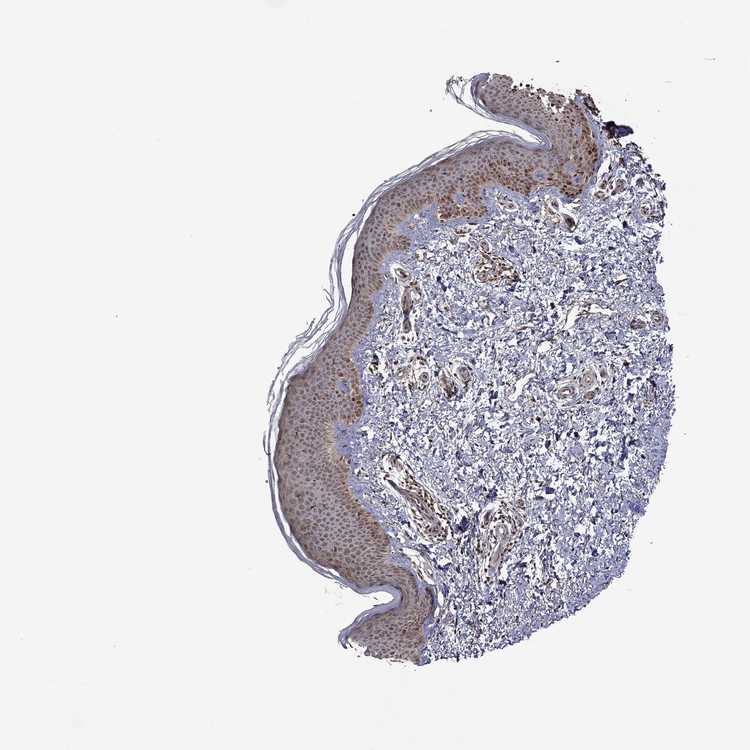

SKIN 1 - Antibody stainingi

Antibody staining in the annotated cell types in the current human tissue is reported as not detected, low, medium, or high, based on conventional immunohistochemistry profiling in selected tissues. This score is based on the combination of the staining intensity and fraction of stained cells.

Each image is clickable and will lead to virtual microscopy that enables deeper exploration of all samples and also displays staining intensity scores, fraction scores and subcellular localization as well as patient and tissue information for each sample.

Antibody HPA029292Antibody HPA071992

Langerhans Not detectedMedium

Fibroblasts Not detectedHigh

Keratinocytes MediumMedium

Melanocytes Not detectedMedium

SKIN 2 - Antibody stainingi

Epidermal cells MediumHigh